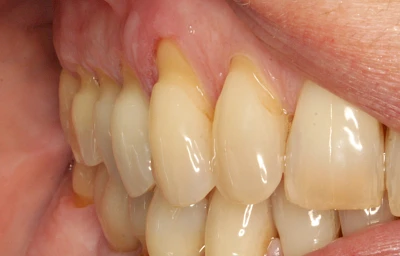

Eine Sonderform sind sogenannte keilförmige Defekte im Bereich der Zahnhälse. Hier geht man davon aus, dass Knirschen und Pressen in Kombination mit falschen Putzgewohnheiten (zu hoher Putzdruck, Verwendung von Zahnpasta mit hohen Abrasionswerten) eine Rolle spielen.